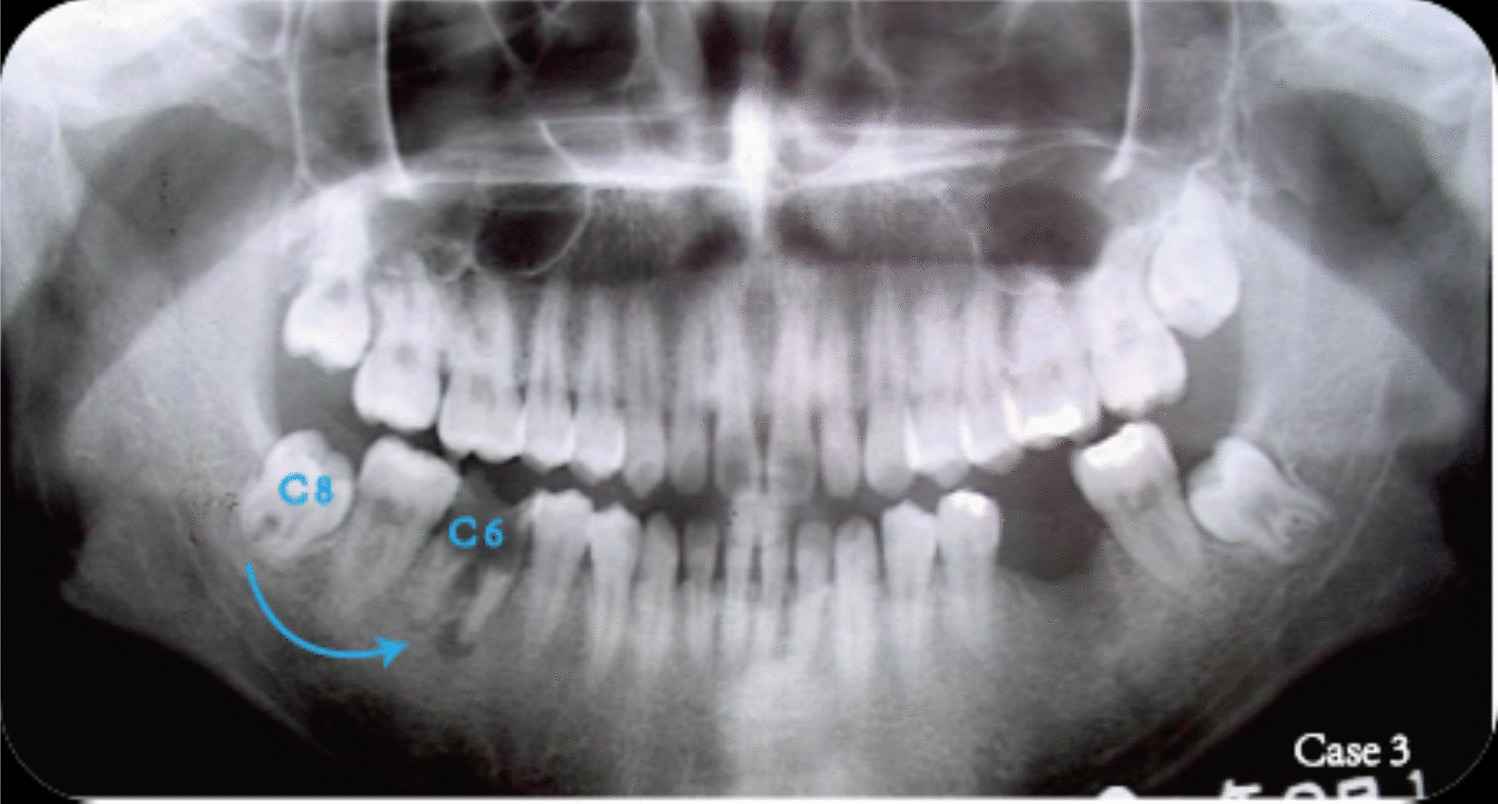

Case 3

A 21-year-old female patient presented to the Oral-Dental Surgery Department of Peking Union Medical College Hospital in September 2002 for the treatment and restoration of her mandibular bilateral first molars. The patient had not received treatment for secondary caries affecting the lower right posterior teeth, leading to disease progression and a gradual evolution into residual crown. Imaging studies indicated a root bifurcation lesion with a small apical dark shadow exhibiting clear borders in tooth 46 (Fig. 16), without evidence of dense bony wall formation. This was diagnosed as a residual crown associated with an apical periapical granuloma in tooth 46. Surgery was planned to replace tooth 46 with tooth 48.

Fig. 16

Preoperative panoramic radiograph and the treatment planning